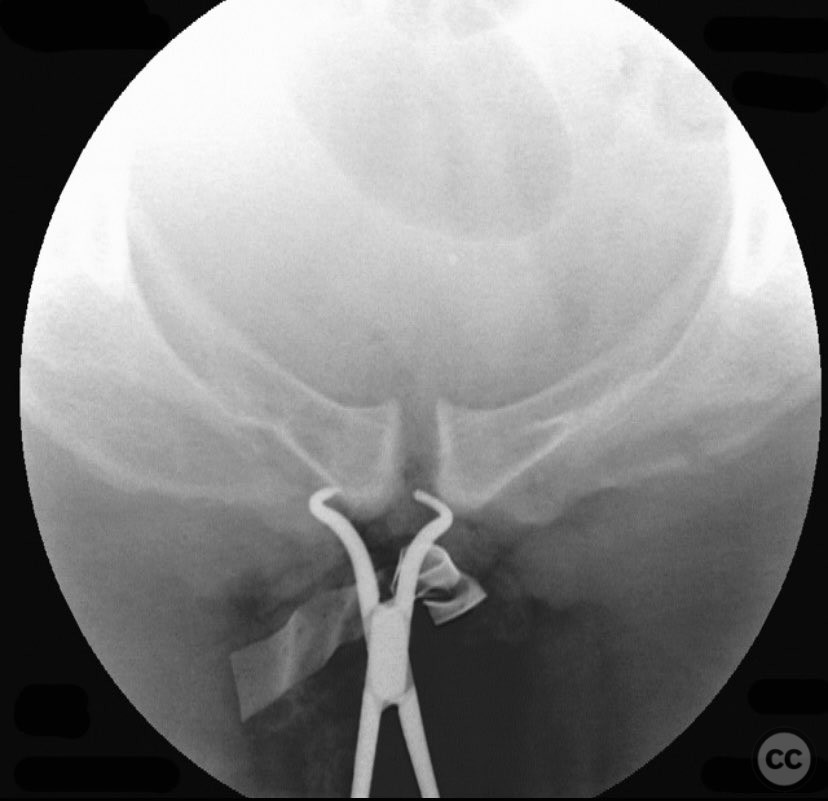

Clinical and radiological findings:  An adult patient sustained traumatic disruption of the symphysis pubis and an incomplete left sacroiliac (SI) joint injury. Initial radiographs and pelvic CT scan (performed without circumferential pelvic wrapping) demonstrated a widened symphysis pubis and an incomplete disruption of the left SI joint. The CT scan further provided information regarding bone quality, upper sacral morphology, patient body habitus, and vascular anatomy. No additional pelvic ring injuries were identified. AO/OTA classification: 61-B2.1 (lateral compression injury with incomplete posterior disruption).

Planning remarks:  The preoperative plan included open reduction and internal fixation of the symphysis pubis via an anterior approach, with provisional reduction using a pelvic reduction clamp. Indirect reduction of the SI joint was anticipated via anterior stabilization; however, preparation for percutaneous iliosacral screw fixation was considered should indirect reduction prove inadequate.